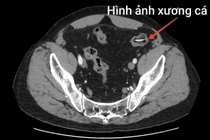

Người đàn ông bị xương cá dài 4 cm đâm thủng ruột non nguy hiểm

Bệnh viện Bệnh Nhiệt đới Trung ương vừa phẫu thuật cấp cứu thành công cho một người đàn ông bị dị vật xương cá đâm thủng ruột non, gây viêm ổ bụng.

Bệnh nhân là ông N.V. N (65 tuổi ở Hà Nội), có thể trạng béo phì, với tiền sử mắc bệnh phổi tắc nghẽn mạn tính (COPD) nhiều năm. Ông phải duy trì thuốc điều trị và hỗ trợ thở máy tại nhà. Ông N. vốn rất thích ăn cá, đặc biệt là cá rán, cá kho - món không thể thiếu trong bữa cơm hằng ngày.

Một ngày trước khi nhập viện, sau bữa tối có món cá rán kho thịt, ông N. bắt đầu cảm thấy đau âm ỉ vùng thượng vị, sau đó cơn đau lan ra toàn bụng. Đến sáng hôm sau, cơn đau tăng dần, lan xuống hố chậu phải, kèm sốt cao (38,5oC). Gia đình đã nhanh chóng đưa ông đến Bệnh viện Bệnh Nhiệt đới Trung ương thăm khám.